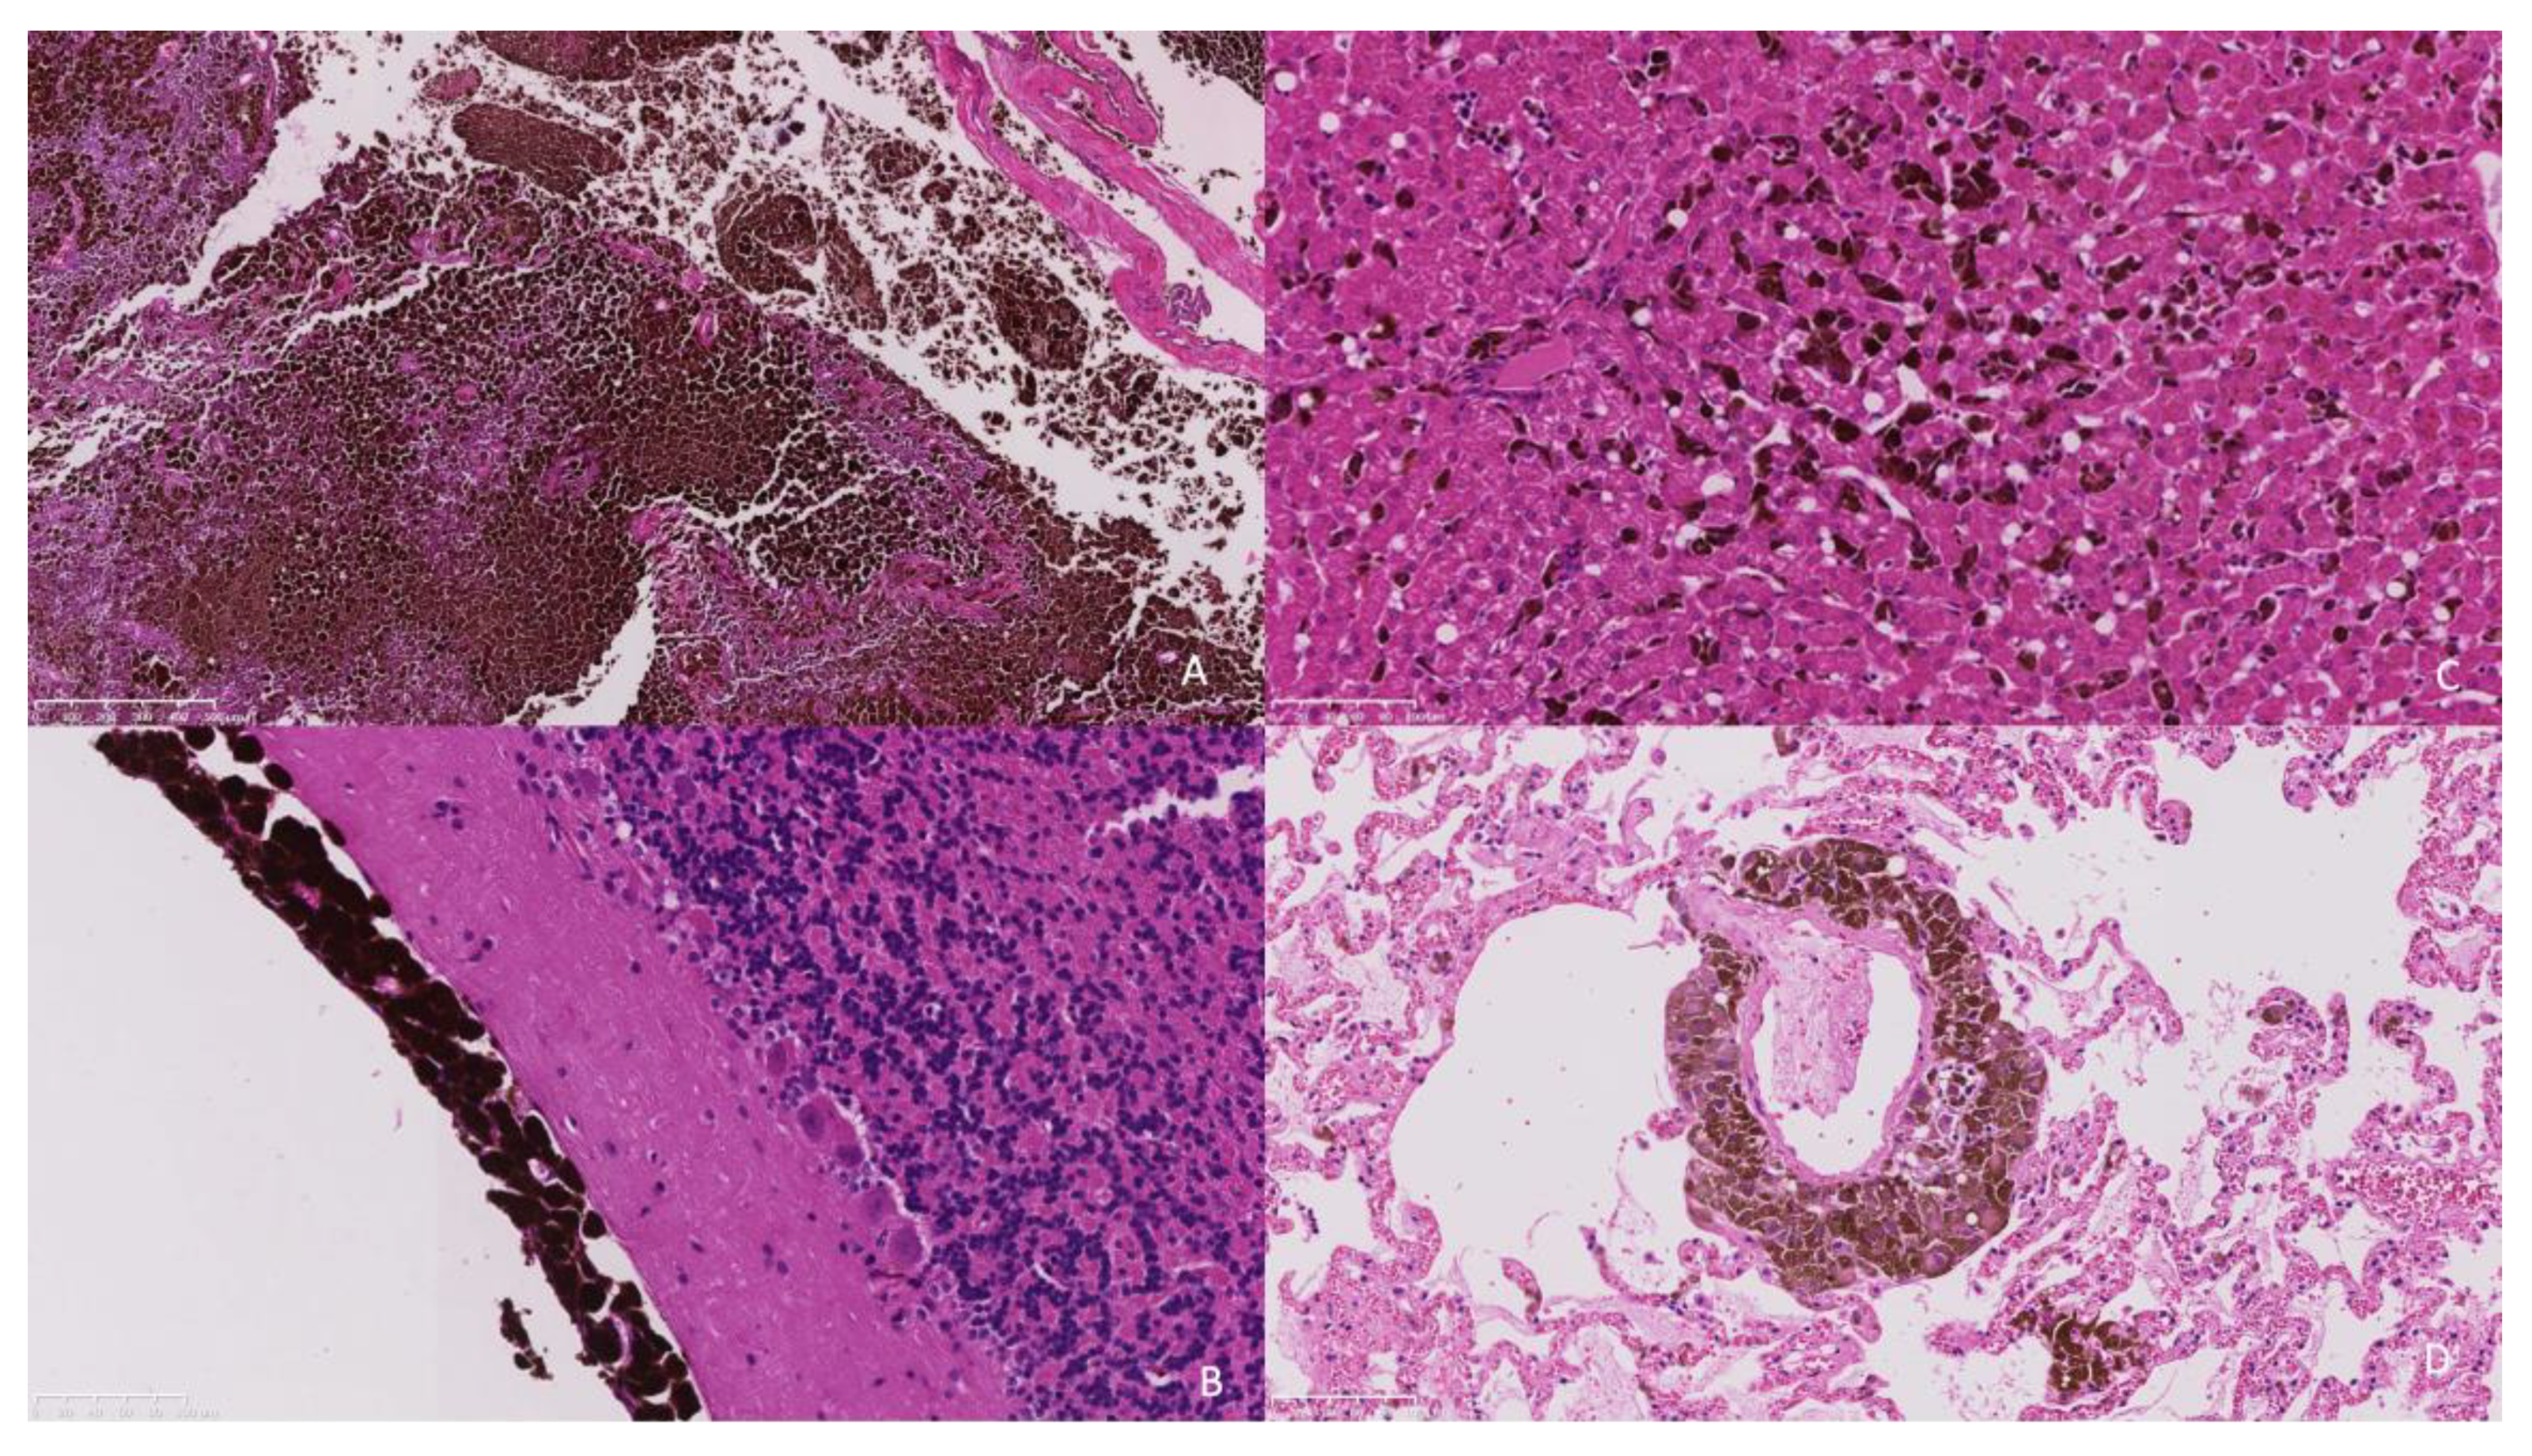

Histopathology of the extra-axial mass identified a moderately well-demarcated, non-encapsulated, densely cellular neoplasm infiltrating and replacing a dense fibrous connective tissue stroma, forming sheets, cords, and nests. Individual neoplastic cells were pleomorphic, predominantly plump spindloid, to round to less frequently polygonal with abundant eosinophilic cytoplasm containing large numbers of brown–black pigment granules (melanin) and a single nucleus. Nuclei were round to oval, with a single prominent nucleolus and stippled chromatin. There was moderate to marked anisocytosis and anisokaryosis, with less than one mitosis identified in 10 high power fields (2.37 mm2). The neoplasm was identified as infiltrating the overlying dura mater, bone, and skeletal muscle. There was a neoplasm with similar histologic features to those previously described, bluntly infiltrating and expanding leptomeningeal layers overlying the cerebral cortices, cerebellum, ventral pons, and medulla. The neoplastic population did not infiltrate beyond the leptomeninges into the subjacent brain parenchyma that otherwise appeared well organised (Figure 4a,b).

Figure 4.

(A). The frontal bone is infiltrated and replaced by an infiltrative pigmented neoplastic population (×5 objective). (B). The neoplastic population is present within the leptomeninges overlying the cerebellum without extension into the underlying neuroparenchyma (×20 objective). (C). The hepatic sinusoids contain randomly distributed neoplastic cells suggestive of embolic spread. (×20 objective). (D). Similarly, the pulmonary interstitium contains randomly distributed tumour emboli. (×20 objective).

Within the liver, multifocally and randomly, hepatocytes were separated by clusters and nests of the neoplastic population as previously described (Figure 4c). The pulmonary interstitium was multifocally and randomly expanded and infiltrated by the neoplastic population (Figure 4d). In the spleen, there was more extensive replacement by coalescing sheets of the neoplastic population. In the kidney, there was an infiltrative, well-demarcated, non-encapsulated neoplasm with similar histologic features to those previously described.